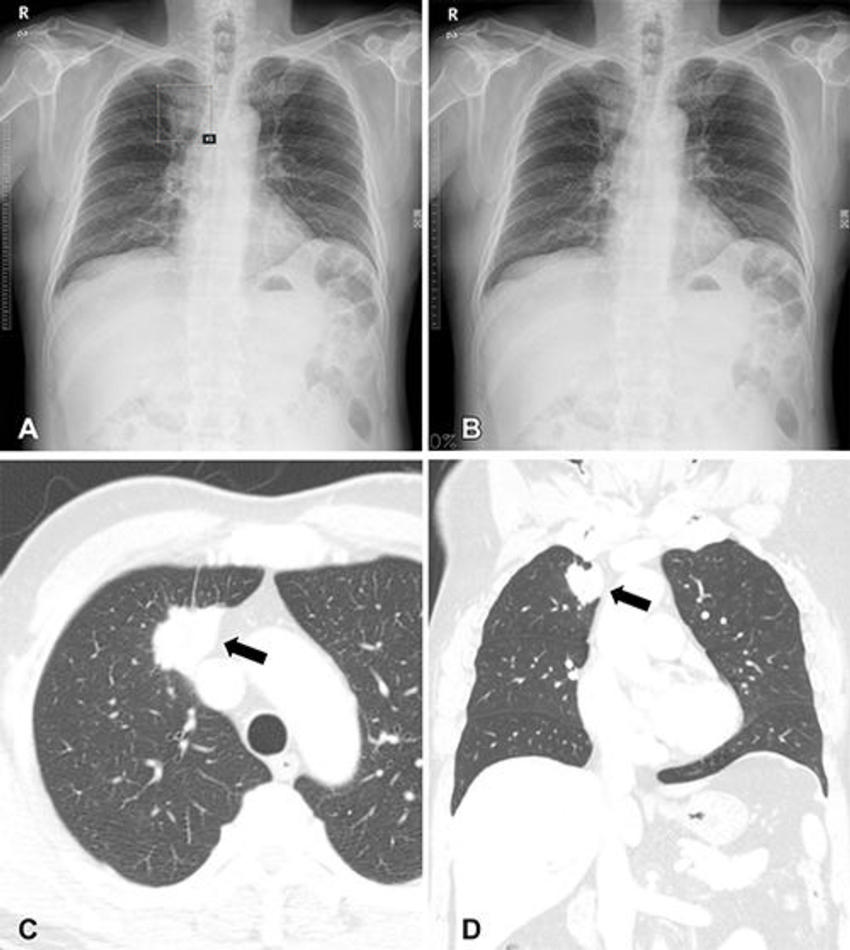

Figure 4. (A, B) Chest radiographs obtained as part of a health checkup in a 65-year-old male patient show reader susceptibility to low diagnostic accuracy performance artificial intelligence (AI). In the first session without AI, a thoracic radiologist with 17 years of experience annotated the mass opacity in the right upper lung zone as lung cancer (box annotation) (A) . Low diagnostic accuracy AI suggested the radiograph as normal (B) . When presented with the AI suggestion at the second reading session, the radiologist changed the decision and determined this radiograph was normal. (C, D) Contrast-enhanced chest CT scans show a 3-cm lung mass (arrow) in the right upper lobe in the axial (C) and coronal (D) planes. The mass was pathologically proven to be invasive adenocarcinoma. Therefore, the reader’s decision was correct in the first session but incorrect in the second session after following the AI suggestion.

High-res (TIF) version